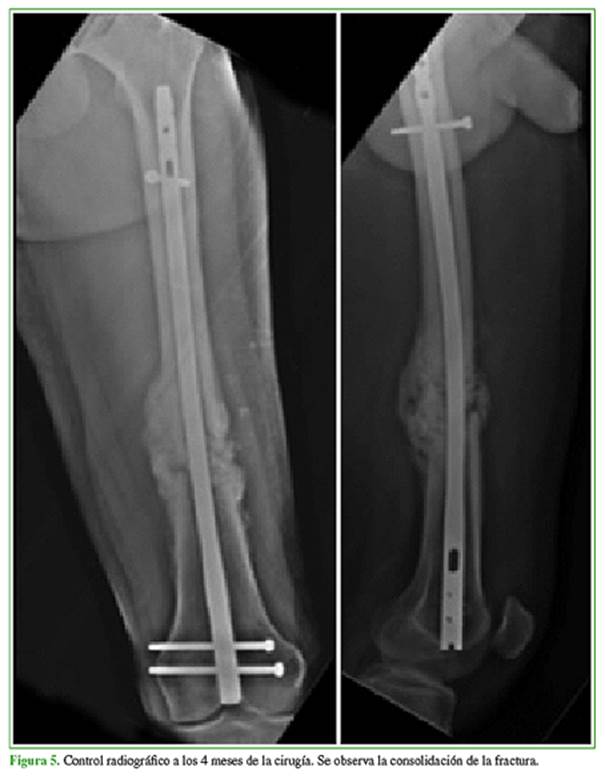

A continuación, se colocó un clavo endomedular retrógrado fresado de 11 mm x 380 mm. Se logró la consolidación a los cuatro meses (Figura 5).